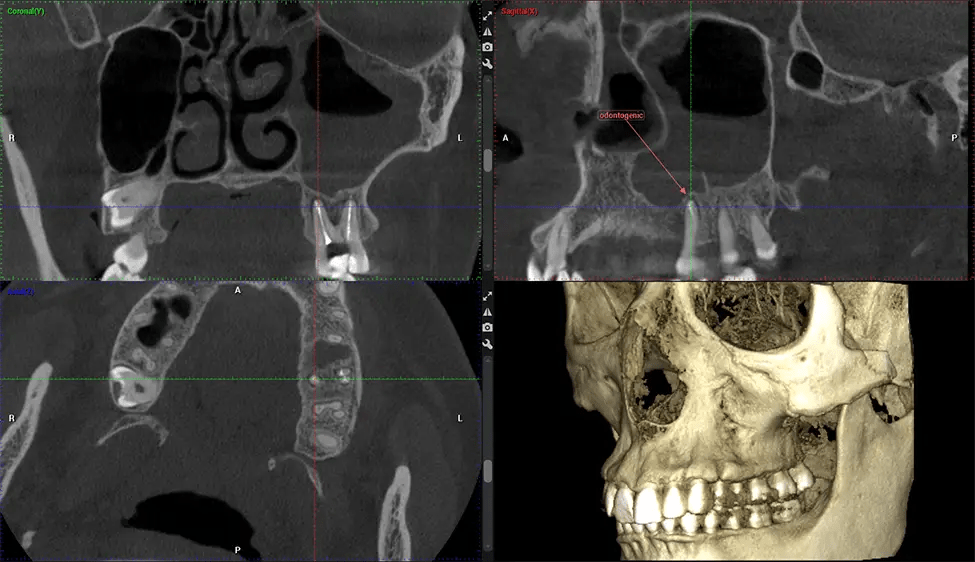

This 3D scan, called cone beam computed tomography, gives your dentist a more complete image of your oral anatomy and disease processes than a traditional X-ray. Unlike conventional X-rays, which capture a 2D image of your mouth from various angles, a 3D scan takes multiple digital X-rays for one image. It provides a complete view of your jaw, teeth, nerves, and soft tissues. This enhanced view allows dentists to detect minor issues not visible in traditional 2D scans, such as impacted wisdom teeth or bone fractures in the sinus cavity.

There are many benefits to using CBCT technology, especially compared to the traditional 2D X-ray format. One of the most significant advantages of CBCT scans is that they provide much more information than traditional X-rays. A scan lets your dentist see images from all angles of your jaw and mouth, including your sinuses, nasal cavity, cheekbones, and other surrounding areas. This added information helps your dentist craft a comprehensive treatment plan that addresses all aspects of your oral health.

Planmeca Viso G7 CBCT ( Cone Beam CT Scan ) is designed to surpass the demands of industry leaders, specialists, and large institutions. It’s has a large ø25×30 cm sensor with four built-in cameras. It can capture unlimited volume sizes from a ø3×3 cm to a ø30x30cm volume capturing the skullcap through C7 on the cervical spine. The Planmeca Viso G7 offers the industry’s largest single volume scan of ø30×19 cm. It’s poised to handle advanced imaging modalities such as Planmeca ProFace® and Planmeca 4D™ Jaw Motion technology. The occipital head support allows an unimpeded view of facial tissue.